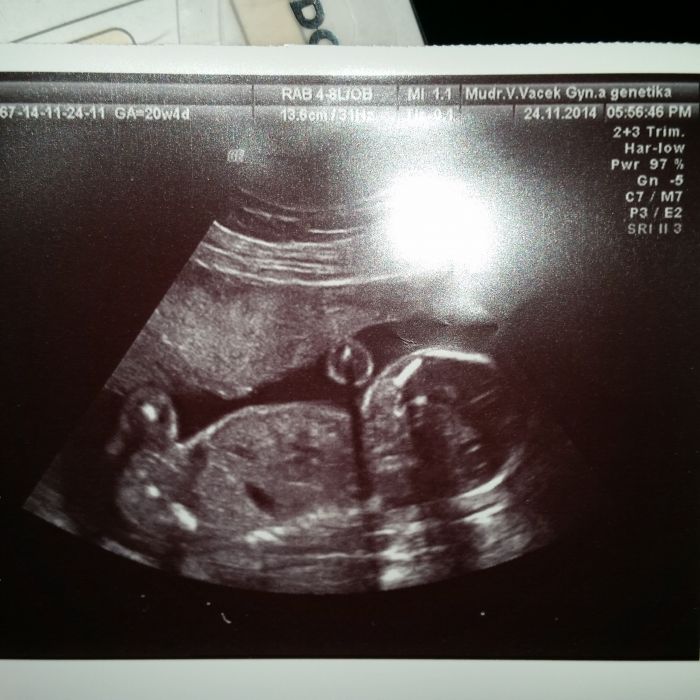

Ahojky holky,tak mame po ultrazvuku.Jsme v poradku.Dokonce jsme vetsi.A i jsme poznali pohlavi jeste drive nezli nam to doktor rekl.Budeme mit kluka :-)

Katty: To je krásná fotečka! Moc blahopřeju! A je super, že už víte, že je to chlapeček - už mu můžete říkat jménem